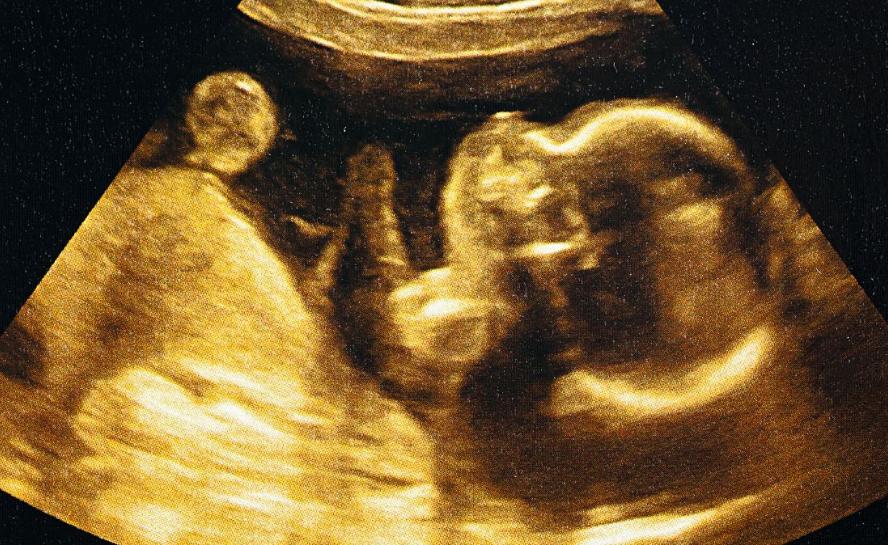

具体每个孕周的HCG情况,可以参照数值表。